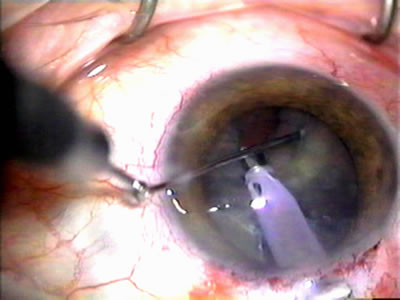

Fig. 5. Anterior chamber angle changes associated with lens extraction and PCIOL This 65-year-old Vietnamese woman has a long-standing history of chronic angle-closure glaucoma treated with laser peripheral iridectomy. The optic nerve demonstrated mild glaucomatous damage and IOP was moderately controlled on two antiglaucoma medications. The cataract was removed through temporal clear corneal phacoemulsification with foldable acrylic IOL. A. Symptomatic cataract in narrow-angle glaucoma eye with patent iridectomy. B. Intraoperative goniophotograph showing crowding of angle with increasing narrowness due to phacomorphic component. C. Intraoperative photograph showing temporal clear corneal approach with IOL in the capsular bag. D. Intraoperative goniophotograph demonstrating deepening of chamber angle following lens extraction. Proposed theories for IOP reduction following lens extraction with complete wound closure:

1. Anterior chamber deepening with improved access to trabecular meshwork

2. Increase in traction on the trabecular meshwork

3. Improved outflow facility mediated by an increase in prostaglandin release

4. Reduction in aqueous humor production

5. Atrophy of ciliary body processes

6. Goniosynechialysis due to intraoperative over deepening of AC with viscoelastic

7. Relief of undiagnosed pupil block